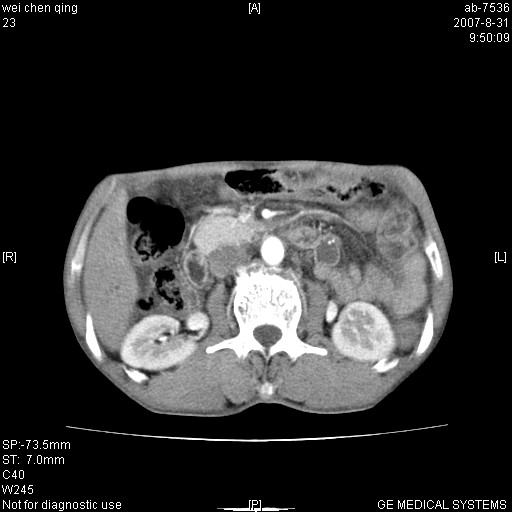

以下是引用zjzjr在2007-8-31 14:38:00的发言:[br]胰头癌伴肝内胆管扩张可能性大。

以下是引用zyyzzy在2007-8-31 14:34:00的发言:[br]该病人肝内胆管扩张,胆囊及胆总管未见明显扩张。在倒数第9层图像上可看到左右肝管结合部(肝总管)有软组织影,此处应薄层扫描。考虑肝总管占位(ca)、腹水。[br]